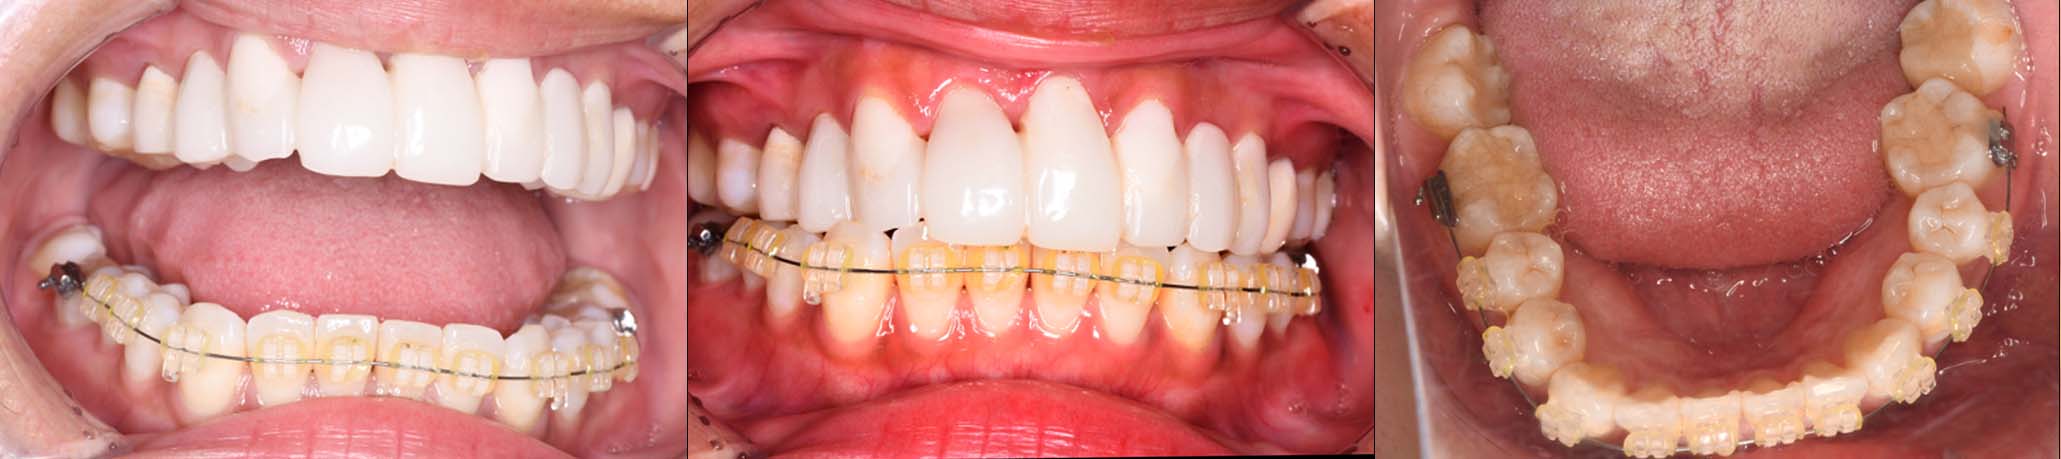

2024年 10月 下顎MTM開始

2024年 10月10日

10月21日